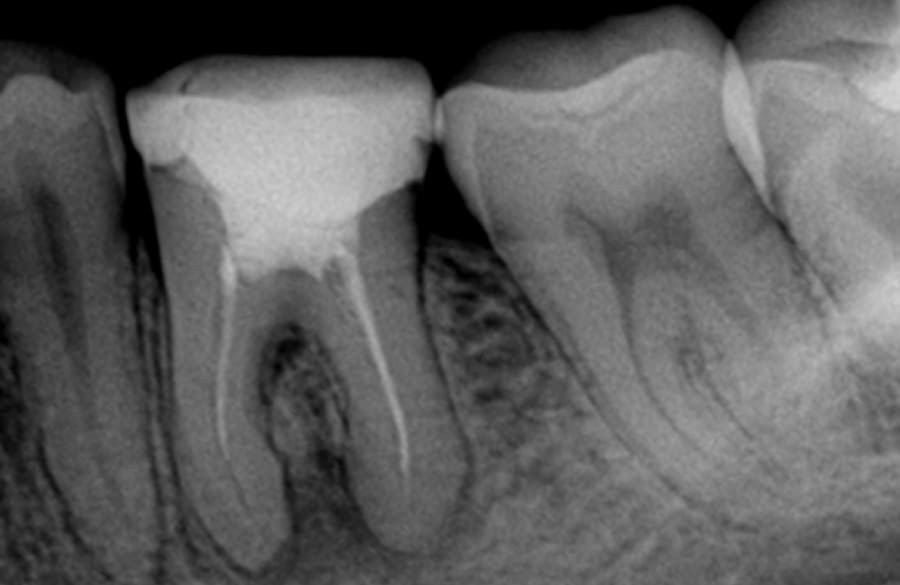

O tratamento de canal consiste na limpeza, desinfecção e selamento do interior do dente — região onde fica o nervo e os vasos sanguíneos. Quando essa área sofre inflamação, o canal precisa ser tratado para evitar dores intensas, abscessos e até a perda do dente.

Esse procedimento, também conhecido como tratamento endodôntico, é essencial para salvar dentes que seriam extraídos em situações mais antigas.